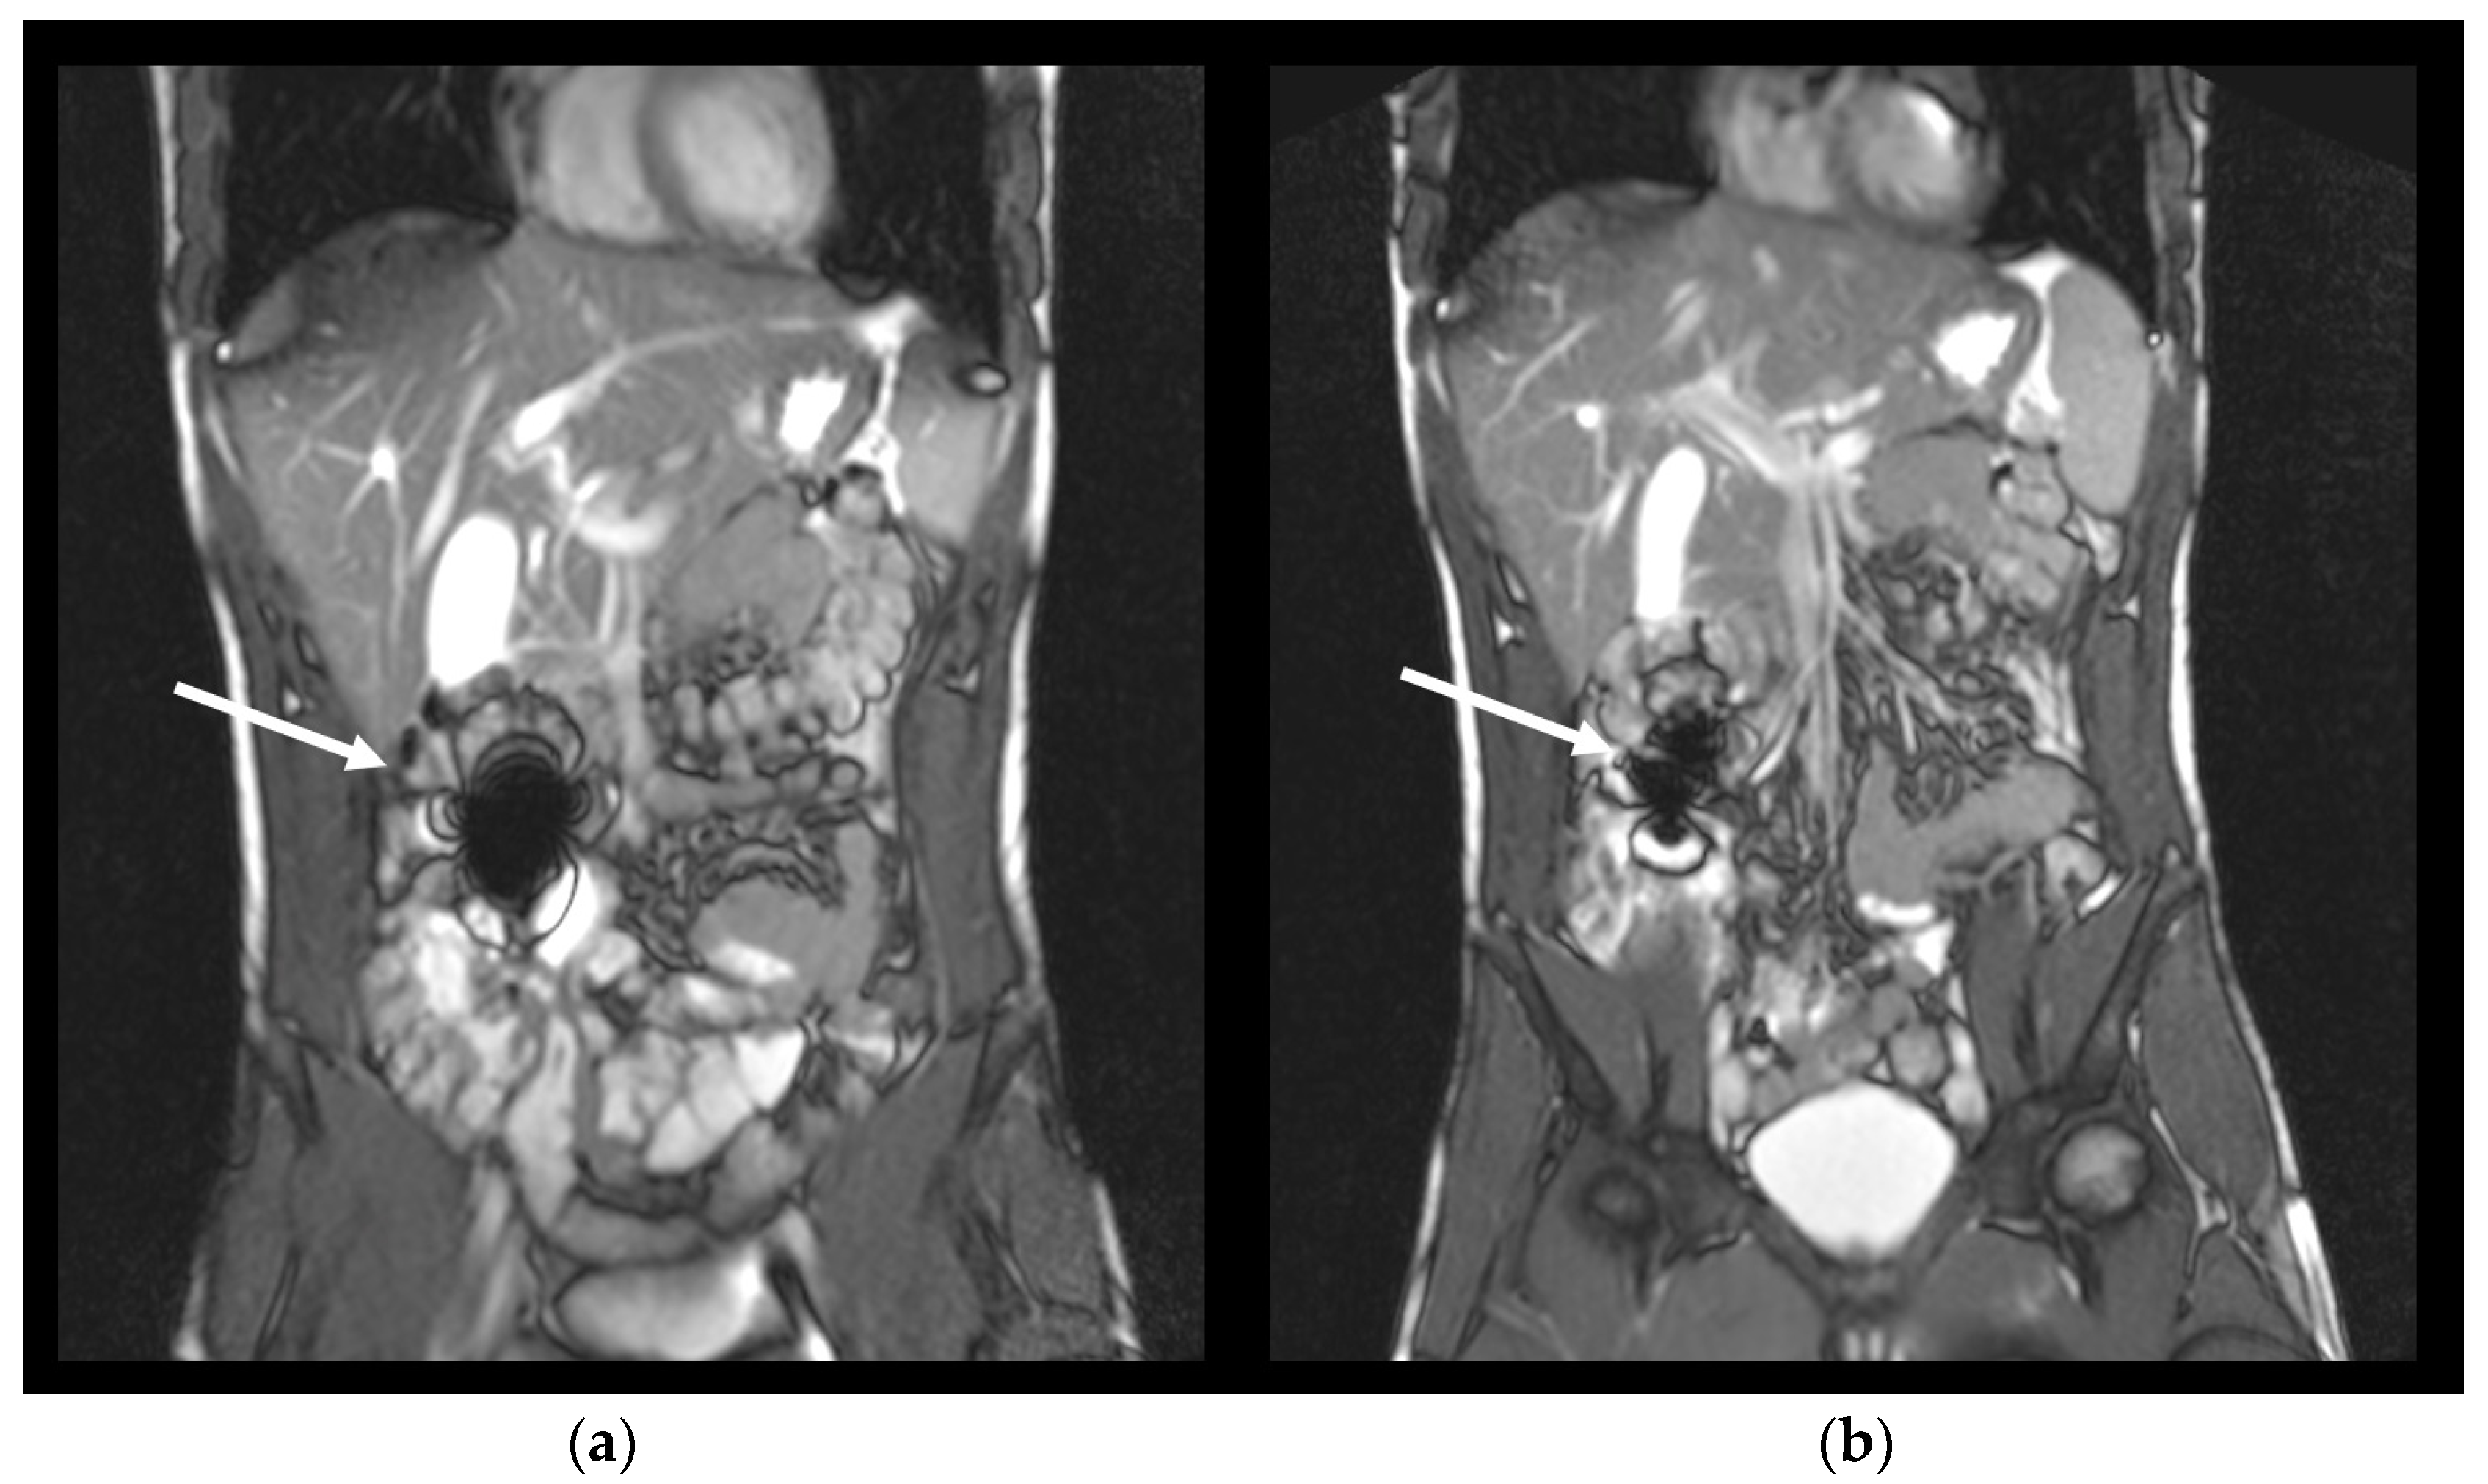

The investigations were performed using a Siemens MAGNETOM Avanto MR-scanner (Siemens Healthcare, Erlangen, Germany) with a field strength of 1.5 Tesla in the Institute of Diagnostic Radiology and Neuroradiology. All measurements were performed in the supine position (subject lying on the back, head forward). A T2-weighted TRUFI sequence was used (Table 2). The susceptibility artifact of iron oxide can be detected clearly with this TRUFI sequence as shown in Figure 1. Transversal and coronal image slices were obtained. Subjects were asked to hold their breath for up to 23 s for each image set to reduce motion artifacts.

Figure 1.

Exemplary coronal images of one volunteer with an intact capsule represented by an intact susceptibility artefact of iron oxide at 75 min after capsule ingestion in the small intestine (a), and the same artefact after disintegration of the capsule at 90 min (b). Arrows show the respective artefact.